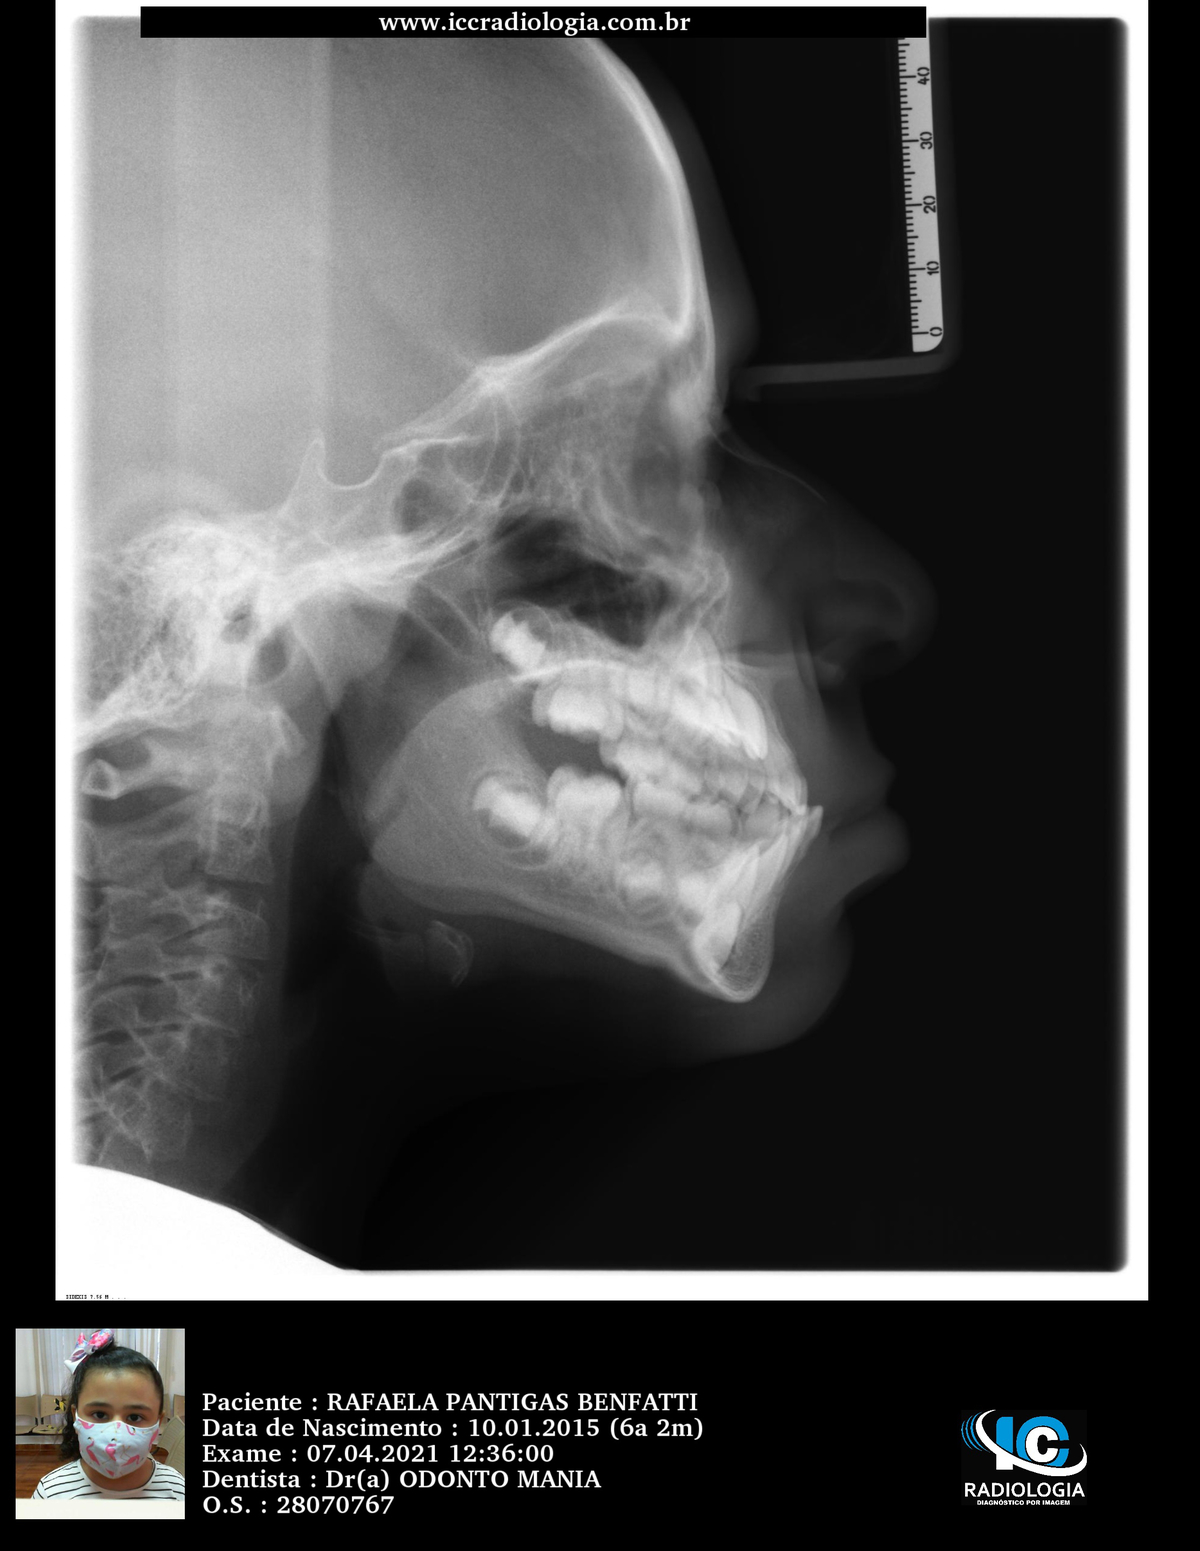

R.P.B.

ORTODONTIA MIOFUNCIONAL